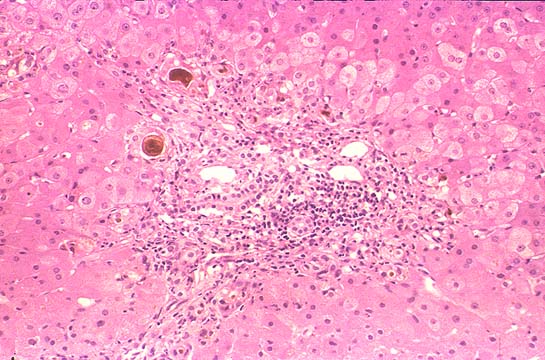

Granuloma of

Mycobacterium

tuberculosis

avium intracellulare

Fig.138-Granuloma of Mycobacterium tuberculosis avium intracellulare

containing only histiocytes. No neutrophils, nor giant cells or caseation necrosis. (PAS stain).